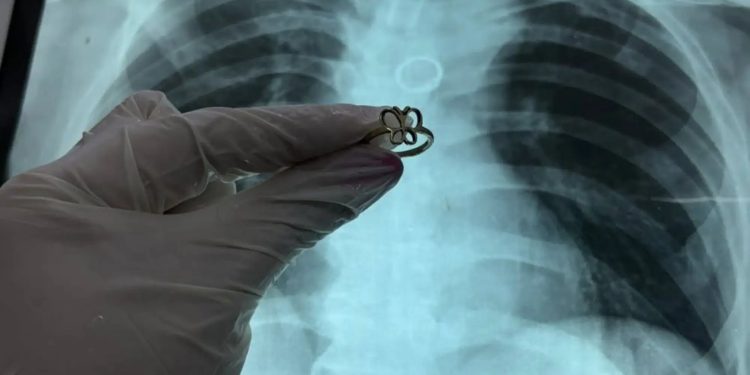

Un hecho inusual se registró en el Instituto Nacional de Enfermedades Respiratorias y del Ambiente Prof. Dr. Juan Max Boettner (Ineram), donde un paciente de 54 años acudió para realizarse estudios tras un accidente de motocicleta y, durante las radiografías, los médicos detectaron un anillo de oro alojado en uno de sus pulmones.

El hallazgo fue confirmado por el doctor Carlos Morínigo, quien explicó que el objeto, con forma de mariposa, fue visualizado inicialmente en una placa de tórax como una figura redondeada ubicada en el bronquio. Posteriormente, mediante un procedimiento de exploración de las vías respiratorias, se logró extraer el anillo.

Morínigo destacó que el material del objeto evitó consecuencias más graves. “Por suerte era de oro, ya que otros metales pueden oxidarse rápidamente en contacto con la mucosa, generando lesiones, fisuras e infecciones severas en los bronquios”, explicó.

El médico indicó que aún se desconoce cómo el anillo llegó hasta el pulmón del paciente, calificando el episodio como un hallazgo inusual.